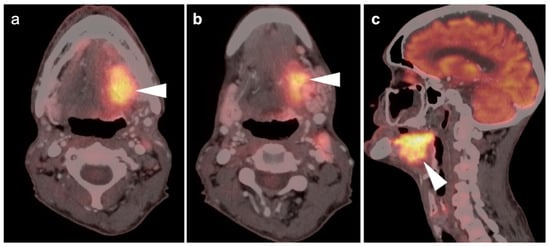

2.3. Nasopharyngeal Carcinoma